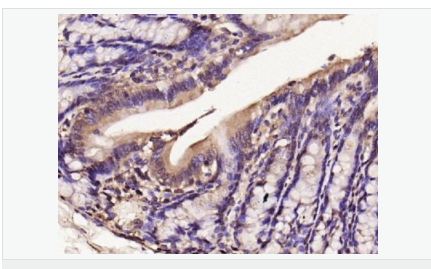

交叉反應(yīng):Human,Mouse,Rat(predicted:Dog,Pig,Horse,Sheep) 推薦應(yīng)用:WB,IHC-P,IHC-F,ICC,IF,Flow-Cyt

| 產(chǎn)品應(yīng)用 | WB=1:500-2000 IHC-P=1:100-500 IHC-F=1:100-500 Flow-Cyt=1μg/Test ICC=1:100-500 IF=1:100-500 (石蠟切片需做抗原修復(fù)) not yet tested in other applications. optimal dilutions/concentrations should be determined by the end user.  |

| 產(chǎn)品介紹 | Nitric oxide (NO) is an inorganic, gaseous free radical that carries a variety of messages between cells. Vasorelaxation, neurotransmission and cytotoxicity can all be potentiated through cellular response to NO. NO production is mediated by members of the nitric oxide synthase (NOS) family. NOS catalyzes the oxidization of L-arginine to produce L-citrulline and NO. Two constitutive isoforms, brain or neuronal NOS (b or nNOS, type I) & endothelial cell NOS (eNOS, type III), and one inducible isoform (iNOS, type II), have been cloned. All NOS isoforms contain calmodulin, nicotinamide adenine dinucleotide phosphate (NADPH), flavin adenine dinucleotide (FAD), and flavin mononucleotide (FMN) binding domains. Nitric oxide synthase is expressed in liver, macrophages, hepatocytes, synoviocytes, stimulated glial cells and smooth muscle cells. Cytokines such as interferon-gamma (IFN), tumor necrosis factor (TNF), interleukin-1 and -2, and lipopolysaccarides (LPS) cause an increase in iNOS mRNA, protein, and activity levels. Protein kinase C-stimulating agents exhibit the same effect on iNOS activity. After cytokine induction, iNOS exhibits a delayed activity response which is then followed by a significant increase in NO production over a long period of time. Human iNOS is regulated by calcium/calmodulin (in contrast with mouse NOS2). Function: Produces nitric oxide (NO) which is a messenger molecule with diverse functions throughout the body. In macrophages, NO mediates tumoricidal and bactericidal actions. Also has nitrosylase activity and mediates cysteine S-nitrosylation of cytoplasmic target proteins such COX2. Subunit: Homodimer. Binds SLC9A3R1. Tissue Specificity: Expressed in the liver, retina, bone cells and airway epithelial cells of the lung. Not expressed in the platelets. Similarity: Belongs to the NOS family. Contains 1 FAD-binding FR-type domain. Contains 1 flavodoxin-like domain. SWISS: P35228 Gene ID: 4843 Database links: Entrez Gene: 4843 Human Entrez Gene: 18126 Mouse Omim: 163730 Human SwissProt: P35228 Human SwissProt: P29477 Mouse Unigene: 709191 Human Unigene: 2893 Mouse Unigene: 10400 Rat Important Note: This product as supplied is intended for research use only, not for use in human, therapeutic or diagnostic applications. 合成與降解(Synthesis and Degradation) 催化生物體內(nèi)一氧化氮(NO)生成的酶。分神經(jīng)型一氧化氮合成的酶(nNOS or NOS-1)、誘導(dǎo)型一氧化氮合成的酶(iNOS or NOS-2)、內(nèi)皮型一氧化氮合成的酶(eNOS or NOS-3)。  |